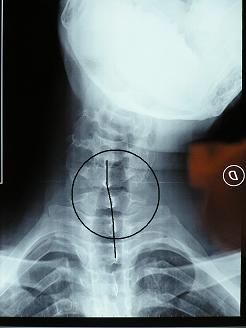

Quando Una Vertebra Non Si Muove, Si Blocca è Sublussata